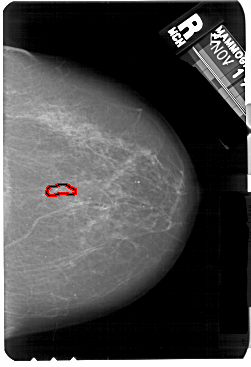

A_1175_1.LEFT_MLO

LEFT_MLO LINES 5491 PIXELS_PER_LINE 3661 BITS_PER_PIXEL 12 RESOLUTION 43.5 NON_OVERLAY

FILE: A_1175_1.RIGHT_MLO.OVERLAY

TOTAL_ABNORMALITIES 1

ABNORMALITY 1

LESION_TYPE CALCIFICATION TYPE PLEOMORPHIC DISTRIBUTION LINEAR

ASSESSMENT 4

SUBTLETY 3

PATHOLOGY MALIGNANT

TOTAL_OUTLINES 1

BOUNDARY